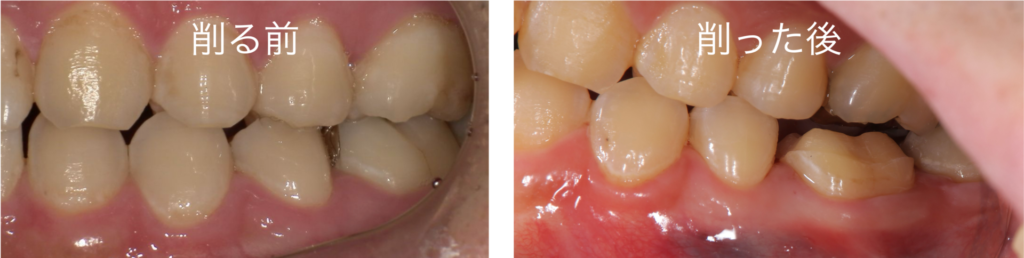

このオーバーレイという治療方法を行う際の、歯の削り方を見てみましょう

このように歯の上部の部分は削ることになりますが、根元に近い部分は削ることなく治療を終えることができます